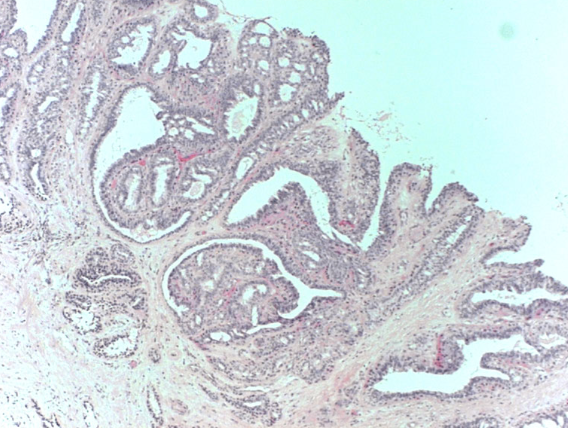

A woman presents with bloody nipple discharge, there is no palpable mass. US is performed

Intraductal papilloma